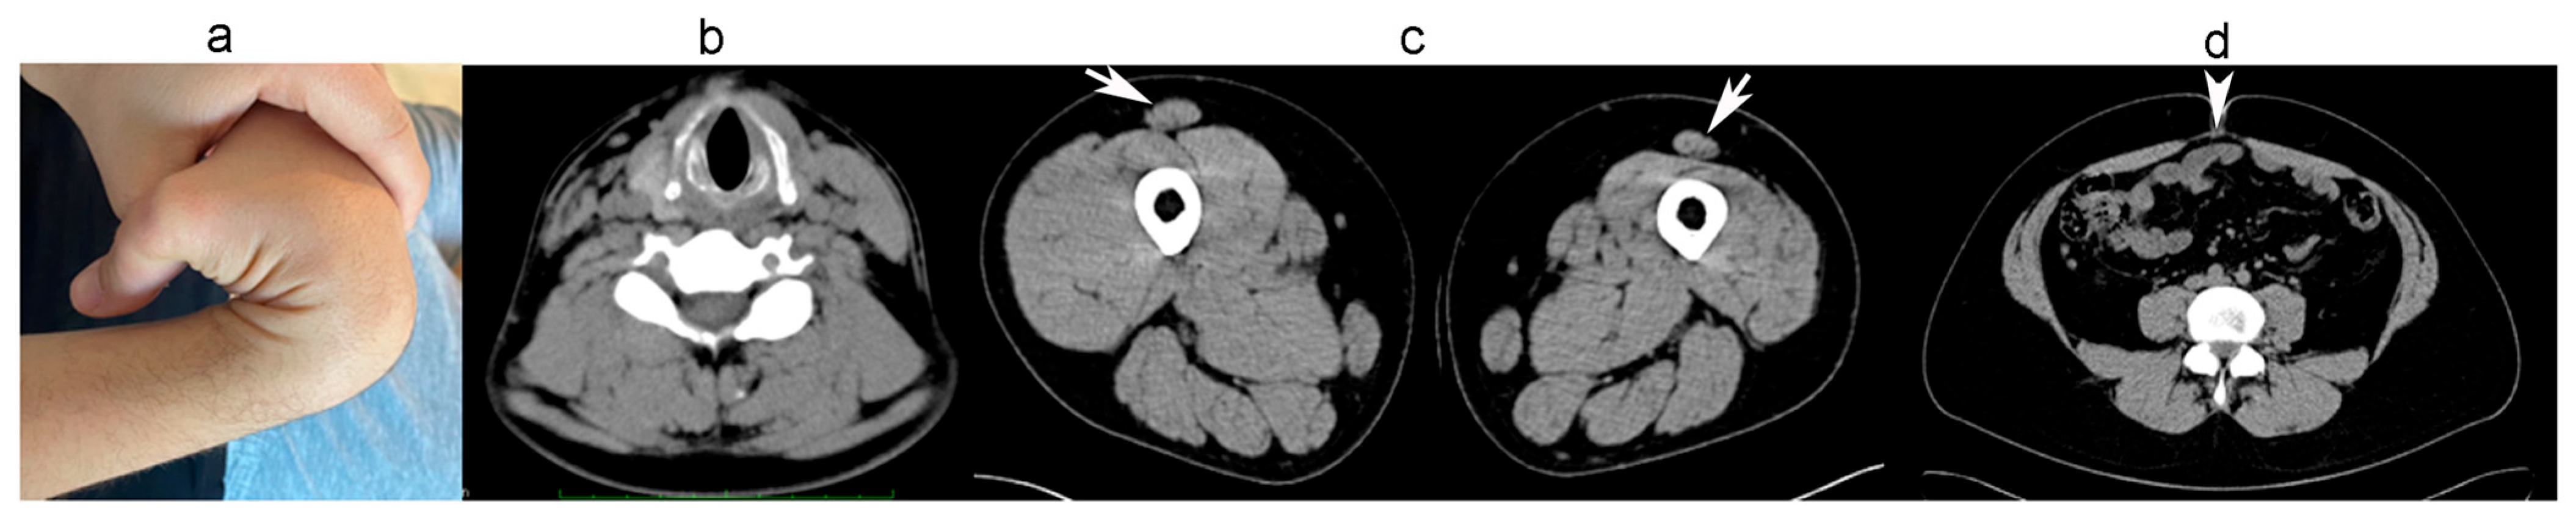

2.1.1. Family A

2.1.2. Family B